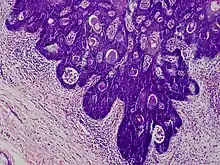

Folliculosebaceous cystic hamartoma abbreviated as (FSCH) is a rare cutaneous hamartoma consisting of dilated folliculosebaceous units invested in mesenchymal elements.[1]: 676 it typically affects adults, have a predilection for the central face or scalp, with less than 1.5 cm dimension.[2] Clinically, the lesions are asymptomatic, rubbery to firm in consistency, and usually occur on or above the neck in (> 90%) of cases, Histopathologically, FSCH shares several similar features to sebaceous trichofolliculoma, but it is usually possible to differentiate these two tumors.[3]